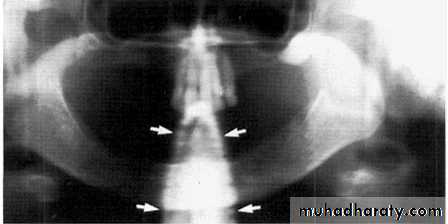

Stud earrings, real shadows (solid arrows)

with ghost shadows (open arrows).

Tongue bar projected over palate

Neck collar artifact

A necklace